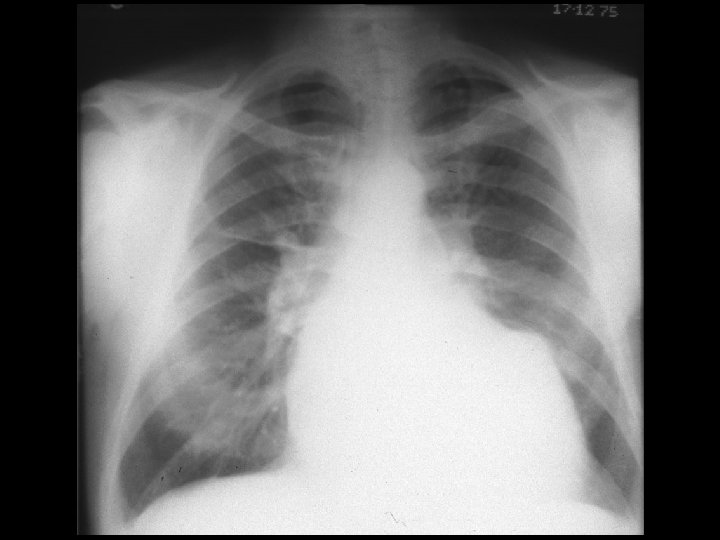

Clínica y diagnóstico o Métodos de diagnóstico por imágenes n Ventriculografía izquierda n Ecocardiografía n TAC n Resonancia magnética

Clínica y diagnóstico o El primer signo de ruptura septal ventricular en post-infarto es la aparición de un soplo pansistólico. Borde esternal inferior izquierdo. RX Tórax: hipertensión venosa pulmonar y aumento del flujo sanguíneo pulmonar.